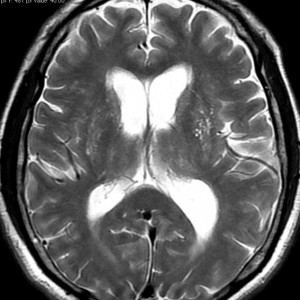

上の写真が小さな聴神経腫瘍とかなり進行した水頭症です。80歳近い男性の患者さんが認知症(痴呆)とまちがえられていました。おしっこをもらしたり,歩行が不安定でよたよたしていました。これは小さな15mmくらいの聴神経腫瘍があるために水頭症になってしまったから起こった症状です。ですから,脳の中に溜った水をお腹までチューブで流すシャント手術という簡単な手術で認知症も歩行障害も治りました。もちろんこの小さな腫瘍は治療する必要がないので何もしないでほっておきました。おそらくかつてはもっと大きな腫瘍だったのでしょう。